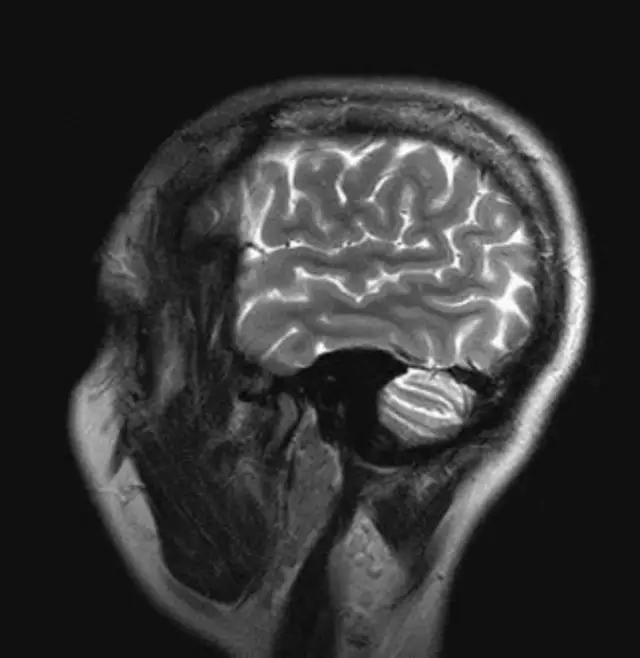

流动(空白)效应:流动液体(血液、脑脊液)不产生信号。

地中海贫血与白血病均为血液系统的问题,主要表现在骨髓,疾病的发病机理有别,MRI表现也不相同;我们可能不是很熟悉这些疾病,也能够从MRI发现区别。图1:正常膝关节 图2:地中海贫血 图3:白血病